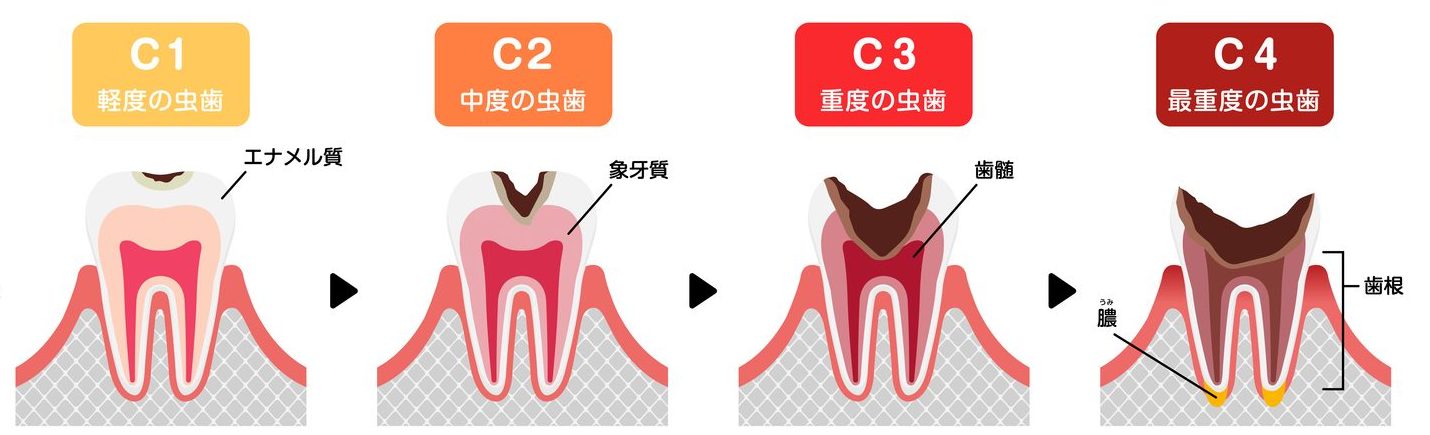

歯の構造と「むし歯」の進行

「歯」の構造は、外側から

- エナメル質

- 象牙質

- 歯髄

の3構造で成り立っています。

直接、目で確認することができる【歯冠】と、歯肉の下に隠れている【歯根】があり、歯は「歯槽骨」と「歯肉」に支えられています。

それ以上に進行してしまったむし歯は、「C」と「数字」を用いて、大きく4つに分類されます。

むし歯の進行:C1〜C4

C1:軽度のむし歯

エナメル質へ進行している状態

C2:中度のむし歯

象牙質まで進行している状態

C3:重度のむし歯

歯髄(神経)まで進行してしまった状態

C4:最重度のむし歯

神経は死んでしまい、根だけになった状態

このような順番で進行していきます。

むし歯は、奥へ進行するほど症状が重度になります。

C0の段階では、進行しないためのブラッシングなどのケアで対応ができますが、C1より進行してしまうと、治療が必要となり自然治癒は期待できません。